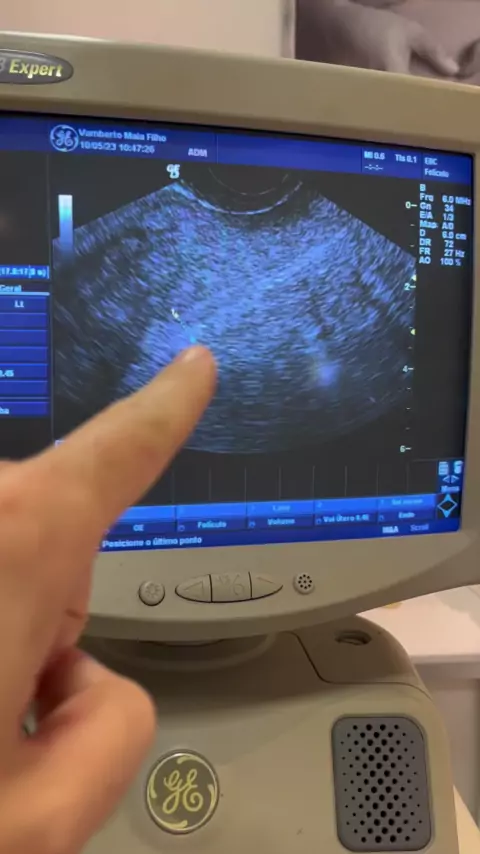

Vamberto Maia Filho

Ter o endométrio fino pode dificultar a gravidez, pois o embrião irá se desenvolver a partir dos substratos desta camada interna do útero, considerada a mais importante para a reprodução. Nesse sentido, quanto mais fino for o endométrio, mais dificuldade a paciente vai ter para engravidar. Um endométrio com espessura adequada deve ter, no mínimo 7 milímetros e, no máximo, de 12 a 14 milímetros (durante a ovulação).